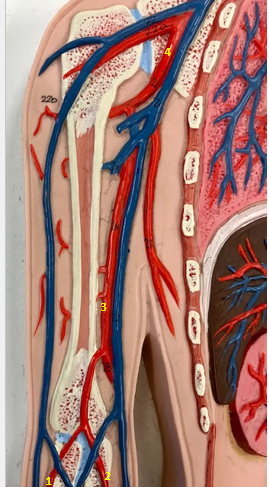

Tunica intima

Name the blue arrow

Lines lumen and release vasoactive chemicals

Function of tunica intima

Venous valves

Name the pink arrow

Prevent backflow of blood

Function of venous valves

Tunica media

Name green arrow

Vasoconstriction and vasodilation

Function of tunica media

Tunica externa

Name the purple arrow

Anchor and bind vessel

Function of tunica externa